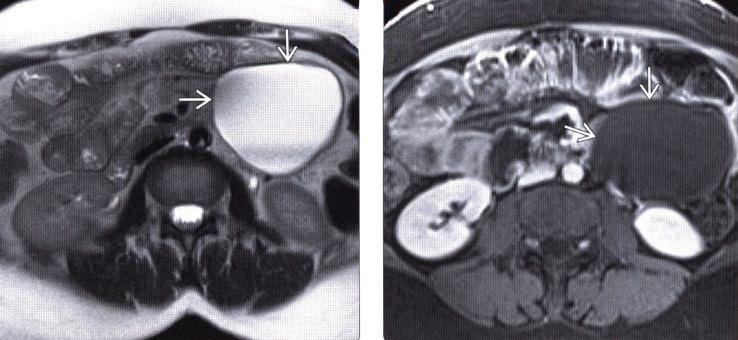

Так может выглядеть забрюшинная лимфангиома ( фото взято в сети Интернет)

8. МРТ-подтверждение. Для дополнительной оценки образования была выполнена магнитно-резонансная томография (МРТ), которая полностью подтвердила кистозный характер находки.

Собрав воедино всю мозаику — отсутствие симптомов, молодой возраст, данные обследования — мы пришли к диагнозу: лимфангиома забрюшинного пространства.

Лимфангиома — это доброкачественная врожденная аномалия развития лимфатической системы, по сути, «киста», стенки которой выстланы клетками лимфатических сосудов. Она медленно заполняется лимфой и может годами оставаться незамеченной. Это образование не обладает злокачественным потенциалом и не перерождается в рак.